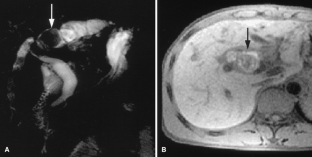

Usual and unusual causes of extrahepatic cholestasis: assessment with magnetic resonance cholangiography and fast MRI

Cholestasis may result from hepatocellular (intrahepatic) disease or biliary tract (extrahepatic) abnormalities. Etiologies causing extrahepatic cholestasis are extremely diverse and invasive procedures, such as endoscopic retrograde cholangiopancreatography (ERCP) and percutaneous transhepatic cholangiography (PTC), were previously required to establish the diagnosis. Due to refinements of magnetic resonance imaging (MRI) techniques, the patient with extrahepatic cholestasis currently can be evaluated noninvasively, and the information revealed frequently exceeds the findings obtained by ERCP and PTC. In this essay, we illustrate the classic MR cholangiographic (MRC) and MRI features of a variety of disorders causing extrahepatic cholestasis, including non-neoplastic disorders of the biliary tract (congenital abnormalities, infectious processes, iatrogenic disorders, and postsurgical complications) and neoplastic conditions (e.g., tumors of the pancreas, biliary tree, liver, ampulla, and regional lymph nodes). In most cases, familiarity with the key MRC features in addition to information obtained via cross-sectional MR images provide sufficient information for adequate lesion characterization.